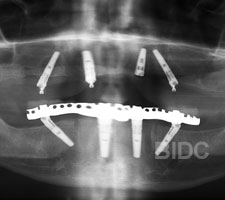

After All-on-4 and All-on-6 cases done at BIDC by implantologists.

2. Installing the implant

If there is existing teeth, teeth are removed. Alevolplasty is commonly done after teeth removal to preserve and shape existing bone. The implant posts is then installed dental implants. The number of implants of 4, 5, 6, or more placed is basded on on bone condition and expected final prothses. If patient requires a temporary dentures during the 3 to 5 days wait time for the fixed hybrid bridge /overdentures, a temporary dentures can be opted prior to start of surgery or your old dentures may be re-lined for wear.